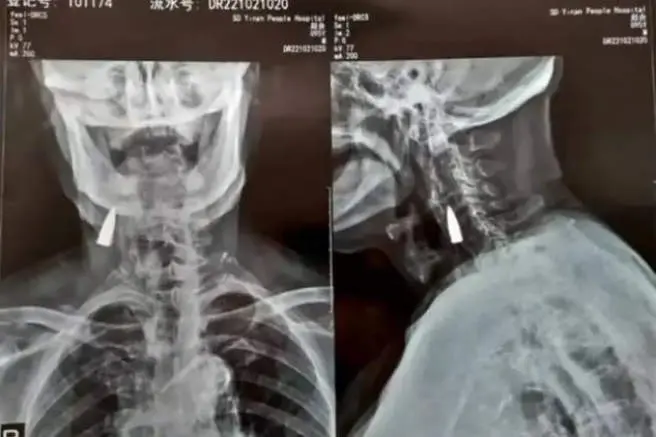

La radiografía del anciano chino de 95 años con la bala en su cuello

Zhao He, veterano de guerra que recientemente sufrió una caída aparatosa desde el balcón de su casa Shandong (China). Tras acudir al médico para hacerse un chequeo de los daños, con una radiografía incluida, el veterano de guerra descubrió para su sorpresa, que llevaba viviendo 77 años con una bala incrustada en su cuello.

Y es que, en un principio, la caída no le causó dolores, pero con el paso de los días comenzó a sentir una leve molestia en el cuello. Su hijo fue quien finalmente, lo llevó al médico para que le chequearan con una radiografía, que les desveló que tenía un cuerpo extraño que más tarde identificaron como una bala vieja.

Wang, su yerno, ha asegurado que "resultó herido mientras transportaba a un camarada herido a través de un río durante una de las batallas", y que  "también hay metralla en otras partes de su cuerpo". Según las sensaciones del propio afectado, esa bala podría haber entrado en su cuerpo por el lado izquierdo de la nariz, perforando su mandíbula superior y arrancándole los dientes antes de alojarse en el cuello.

Al determinar que la bala se encuentra cerca de algunos vasos sanguíneos importantes y que hasta el momento no había ocasionado ningún problema, los médicos comunicaron a Zhao He que lo más adecuado sería dejarla dentro. "He estado sano siempre, así que no hay razón para cambiar las cosas ahora", aseguró el anciano.